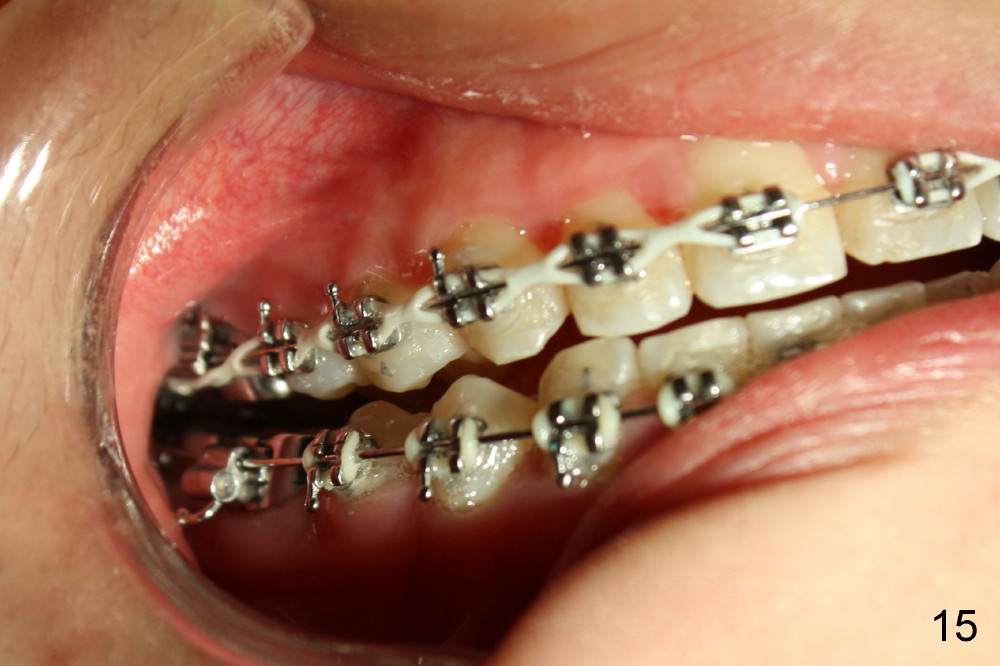

Another one month later, UL2 is moved labially and a bracket is placed (upside down in order to fix torque problem associated with cross bite correction). Surprisingly, it works perfectly: UL2 orientation is right (Fig.12,13,14). The distal diastema (Fig.14 <) is to be closed by power chain. The palatal expander is removed since the posterior cross bite has been a little overcorrected (Fig.14,15, as compared to Fig.1,2,4-7).